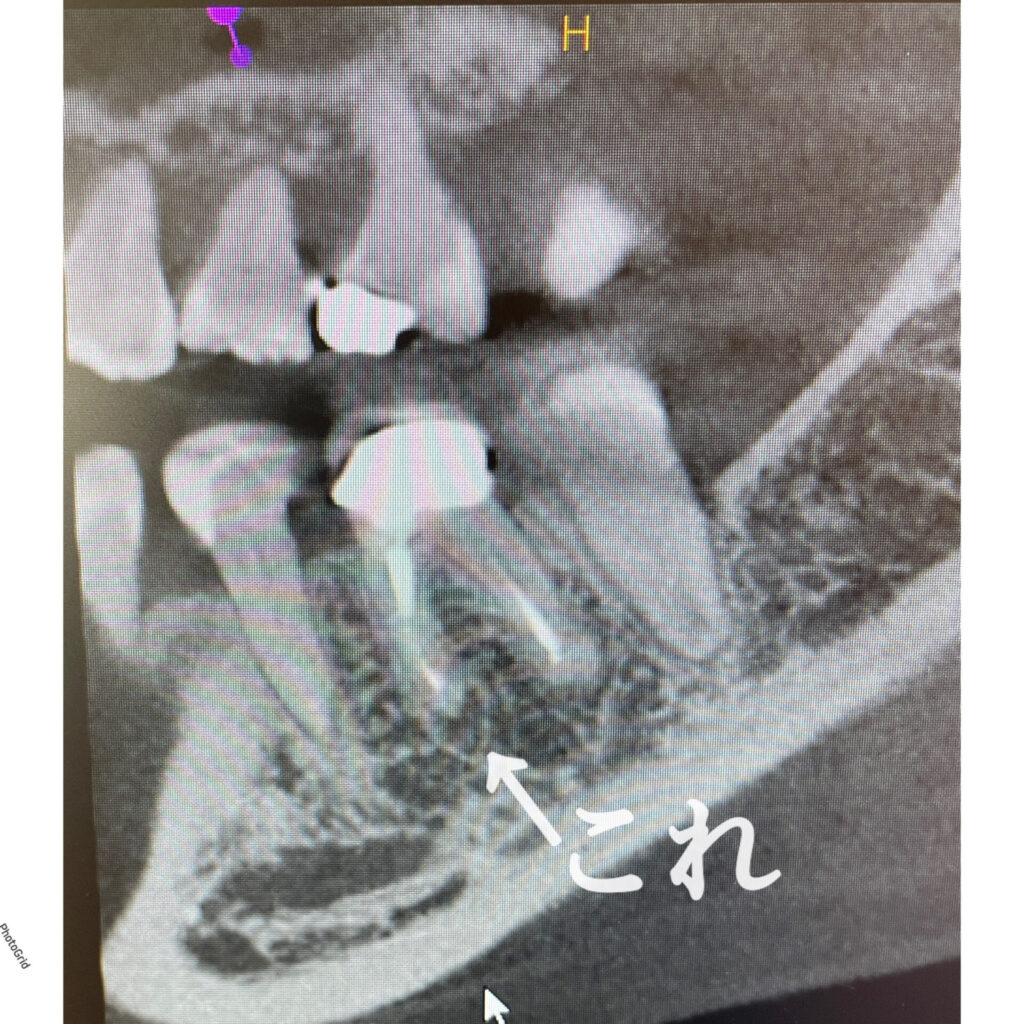

奥歯のやりかえです。真ん中に写っている左下奥歯(左側下顎第一大臼歯)の再治療です。神経治療からやり直しています。*色彩セラミックプラン